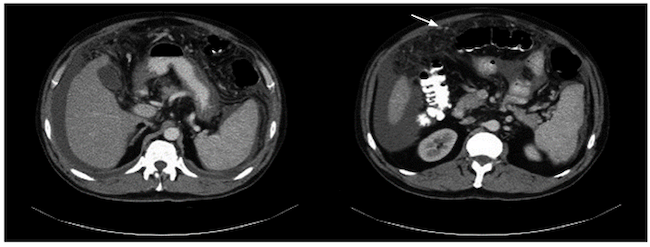

El citoquímico del líquido ascítico mostró un gradiente de albúmina suero-líquido (GASA) de 0,6 compatible con ascitis no hipertensiva; leucocitos de 2400/mm3, 100 % linfocitos, con glucosa en 82,4 mg/dL y coloración de Gram negativa para gérmenes. Se amplió el estudio con niveles de adenosina-desaminasa (ADA) en el líquido peritoneal con un valor de 102 U/L (referencia < 36 U/L) y el citológico mostró linfocitosis y fue negativo para malignidad. Se realizó una tomografía axial computarizada (TAC) de tórax y abdomen con el fin de descartar una neoplasia como diagnóstico diferencial. La TAC de abdomen mostró cambios en la densidad del peritoneo con engrosamiento, múltiples nódulos pequeños en el tercio superior del abdomen que realzaban con el medio de contraste (Figura 1), hígado pequeño y ascitis abundante; y la TAC de tórax mostró escaso derrame pleural bilateral. Se definió realizar una laparoscopia para la toma de biopsias en la que se evidenció un compromiso extenso de todo el peritoneo por micronódulos amarillentos, algunas adherencias interasas, abundante líquido verdoso no purulento en la cavidad, así como hígado de aspecto cirrótico con algunos micronódulos; se tomó biopsia de peritoneo e hígado. El estudio histológico del peritoneo fue compatible con inflamación granulomatosa, con tinción de Ziehl-Neelsen (ZN) negativa (Figura 2), pero con reacción en cadena de la polimerasa (PCR) positiva para Mycobacterium tuberculosis. El enzimoinmunoanálisis de adsorción (ELISA) para VIH fue negativo.